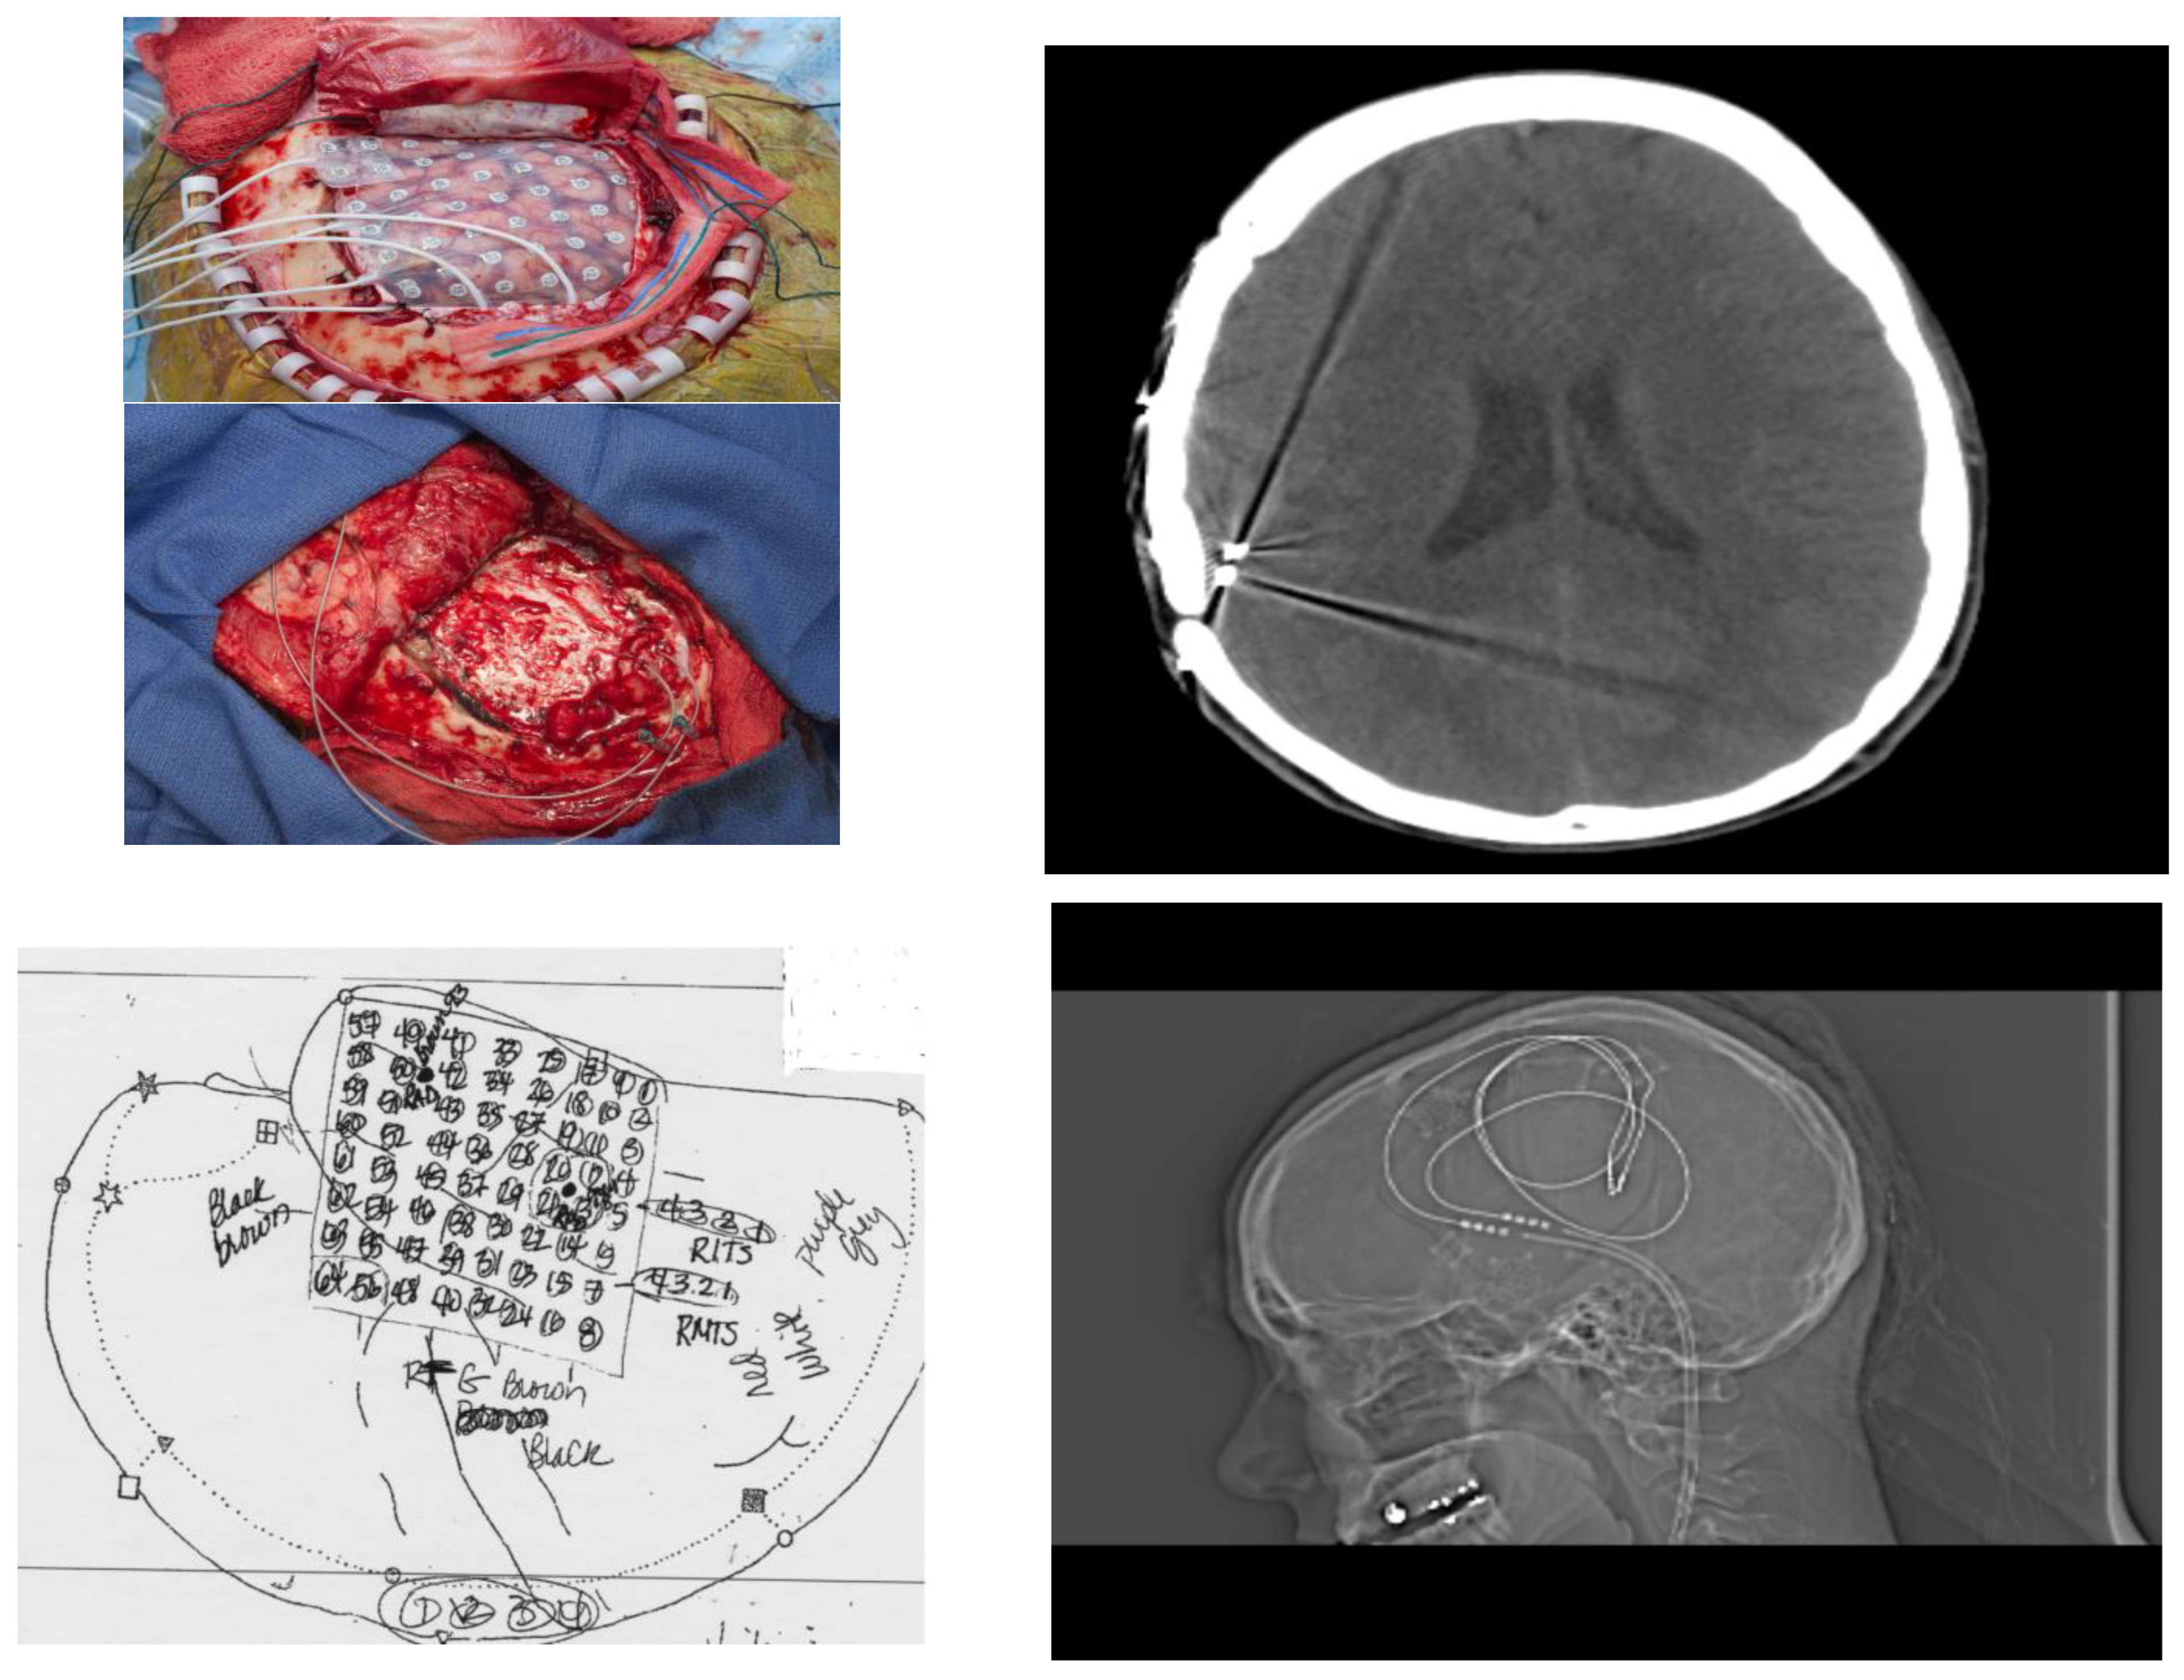

The patient had a stereotactic MRI for surgical planning purposes which again showed signal abnormality in the subcortical white matter of the posterior superior aspect of the right superior temporal gyrus near the junction with the superior marginal gyrus, most likely representing cortical dysplasia. The patient had implantation of intracranial electrodes in the right temporal region including an 8 × 8 right temporal grid and two four-contact right temporal depth electrodes as well as two four-contact right inferior temporal strip electrodes. She subsequently had video/EEG monitoring. This showed right posterior temporal spikes and sharp waves and numerous clinical seizures with onset in the right posterior temporal region at the junction of parietal and occipital cortex. She also had extra-operative cortical stimulation for functional cortical mapping. Eloquent cortex related to speech and language processing was mapped underneath the right temporal grid. These areas of the eloquent language cortex overlapped with her epileptogenic zone. For this reason, a trial of sub-threshold stimulation of the right temporal depth electrodes and the right temporal grid electrodes was carried out, which seemed to be beneficial in suppressing her interictal epileptiform discharges [18]. Consequently, she had removal of her intracranial electrodes and the placement of two right temporal depth electrodes and a brain stimulator. She did well following the surgery, achieving ILAE outcome 3 (Figure 4).

Figure 4.

Operative Evaluation and Implantation of Neuromodulatory Technology. (Left, top) Patient underwent phase 2 intracranial electrode implantation with pre-planning (schematic Left, bottom). After identification of temporo-parietal-occipital junction seizure onset zone and with understanding from prior fMRI that this was eloquent cortex, neuromodulatory technology was implanted and visualized with CT scan and XR (Right top; Right, bottom respectively).